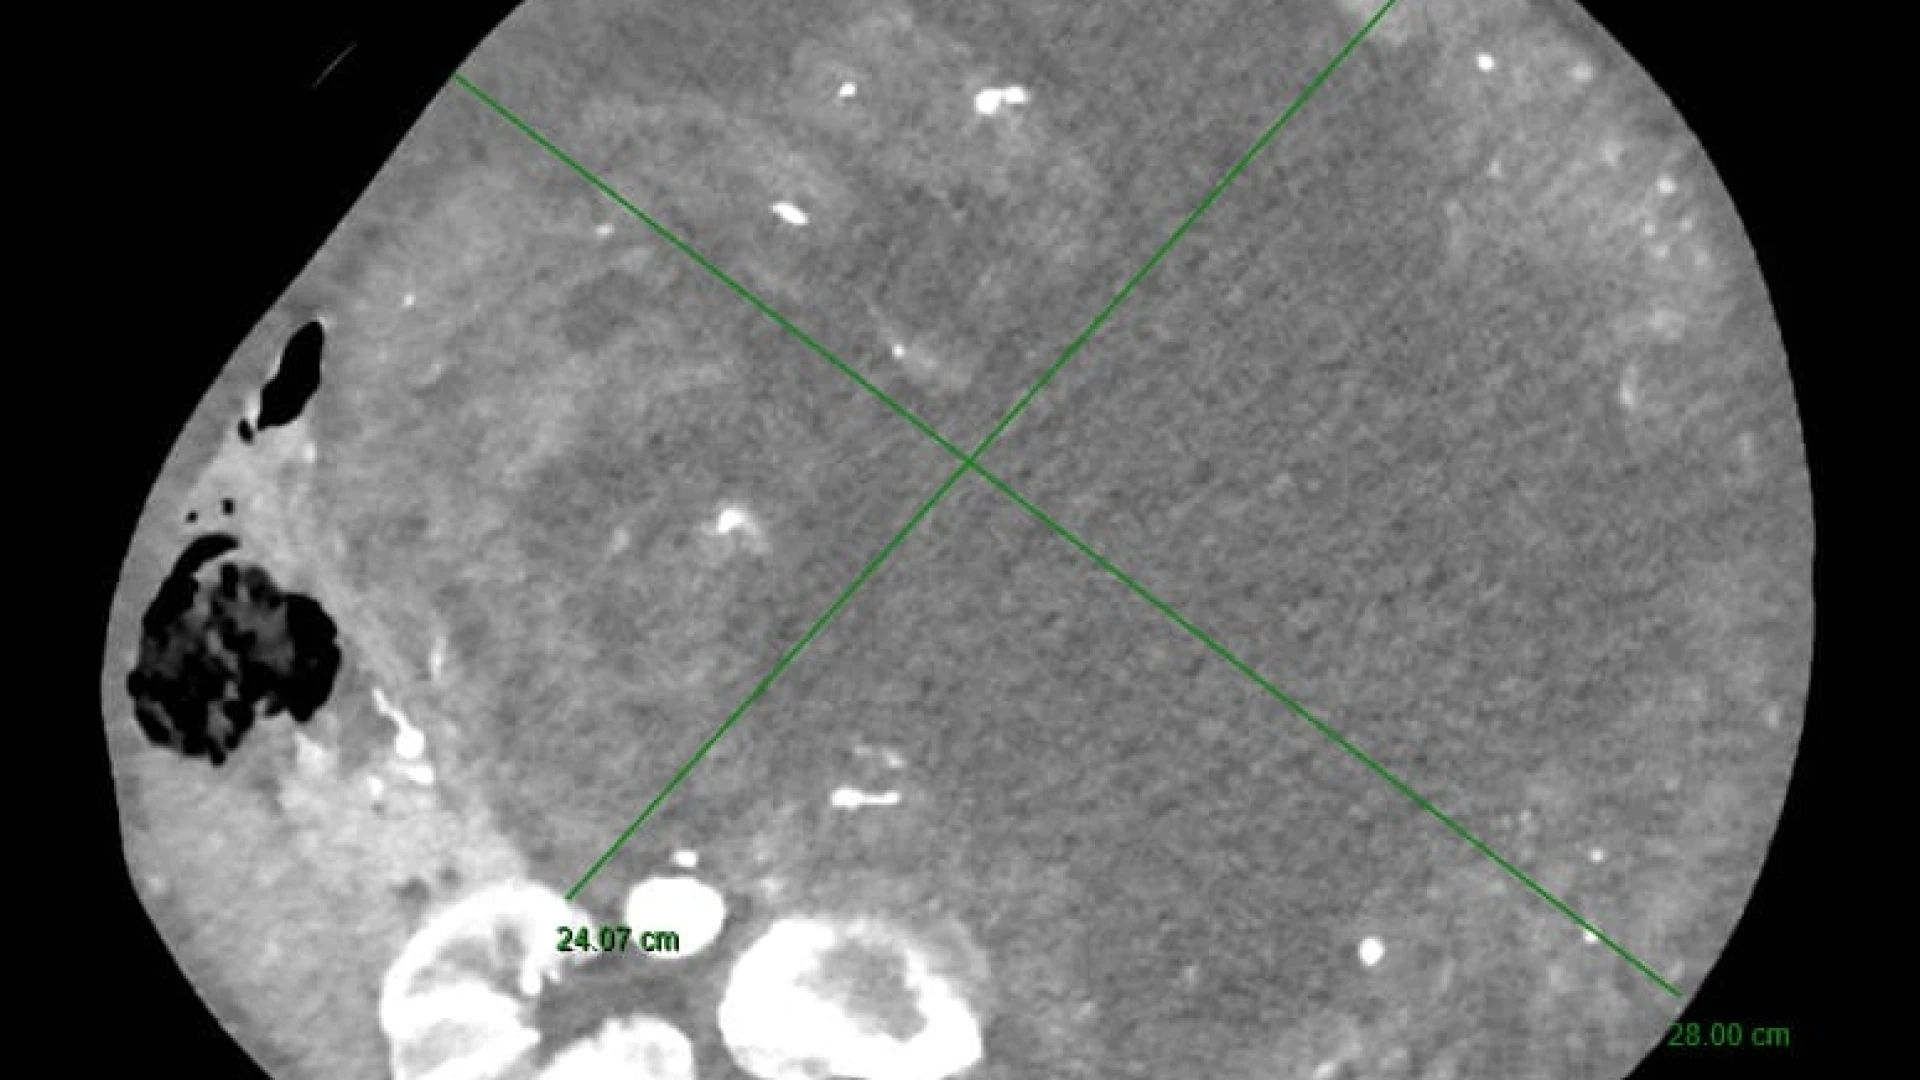

Tutto è iniziato da un disturbo apparentemente comune: la stipsi. La paziente si era infatti rivolta per la risoluzione del problema al Prof. Guido Sciaudone, Direttore della SC di Chirurgia Generale, che la aveva visitata presso l’ambulatorio di Chirurgia Colo-Rettale ed Oncologica della ASREM da lui diretto. Tuttavia, alla visita clinica era da subito apparso evidente che il sintomo stipsi era secondario alla presenza di una voluminosa massa addominale di dimensioni spropositate che i successivi accertamenti diagnostici rivelavano essere a partenza dal rene sinistro. Tale massa – paragonabile a un grosso cocomero – occupava ormai l’intera cavità addominale, comprimendo oltre all’intestino tenue ed al colon, organi importanti quali il fegato, la milza, lo stomaco, il pancreas ed il duodeno e compromettendo la circolazione sanguigna di tali strutture.

L'operazione, delicatissima, che ha richiesto estrema precisione, ha previsto diverse procedure integrate: la nefrectomia totale con l'asportazione del rene inglobato nella massa di verosimile natura eteroplastica (si è in attesa dell’esame istologico definitivo), la colectomia subtotale (cioè la rimozione di gran parte del colon in quanto ischemico in seguito all’occlusione cronica ed alla sofferenza vascolare dovuta alla compressione dei vasi da parte della massa) ed il confezionamento di una derivazione intestinale esterna per permettere la canalizzazione.